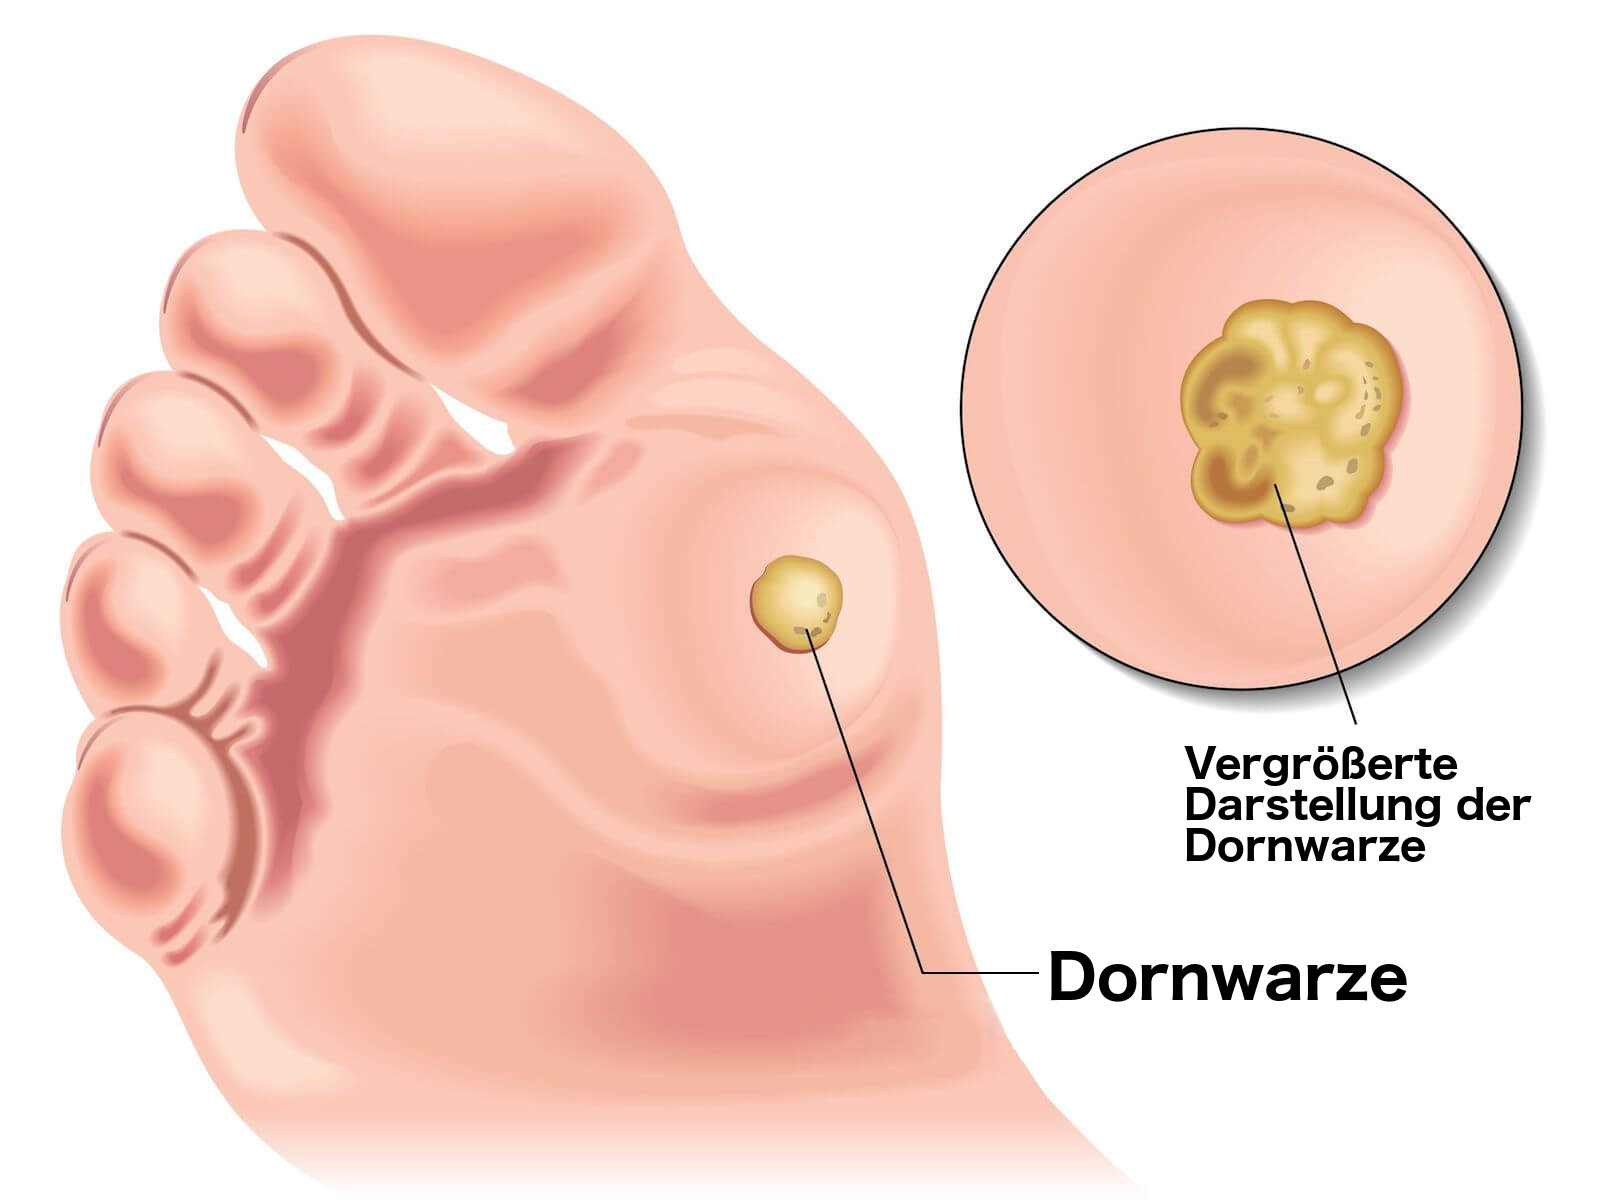

Симптомы кондилом могут варьироваться, и визуальное представление этого заболевания может быть различным. Некоторые кондиломы выглядят как небольшие бугорки или бородавки, в то время как другие могут иметь форму плоских пятен или цветных наростов.